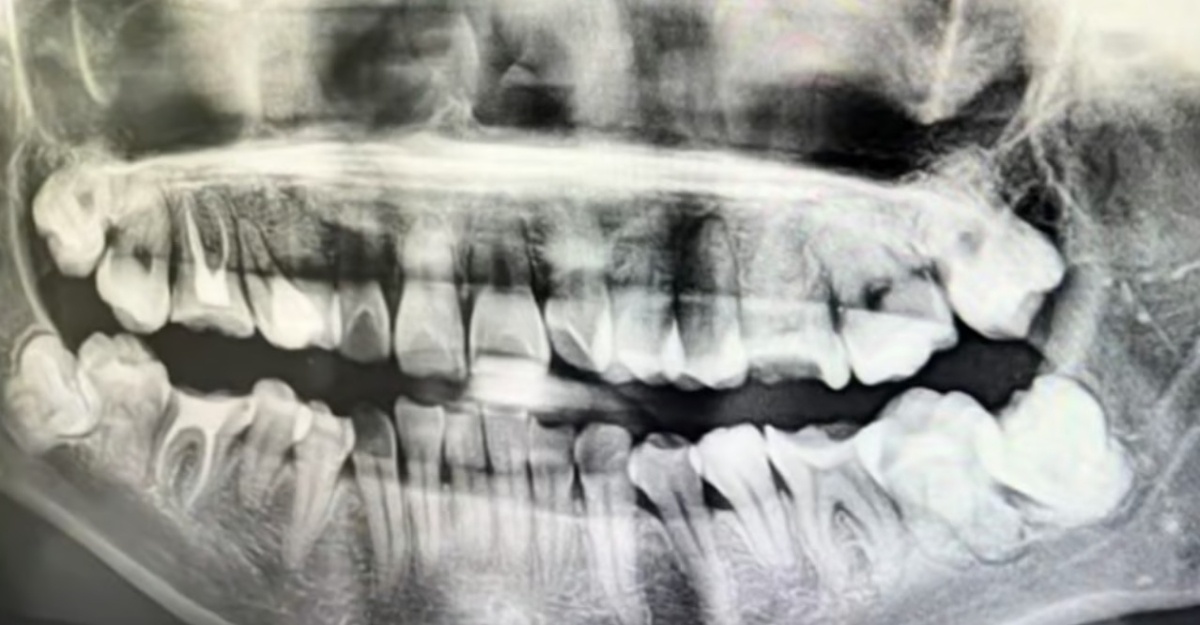

Doktor Salah Cabut Gigi, Wanita Tahan Sakit Terjatuh Dari Tingkat 11

Menurut South China Morning Post, mangsa yang berasal dari wilayah Anhui telah menjalani prosedur di Hospital Perbandaran Anqing untuk mencabut gigi geraham bongsu pada 12 Mac lalu.

Bagaimanapun, doktor yang bertugas melakukan kesilapan dengan mencabut gigi yang sihat sebelum memasukkannya semula secara paksa, malah mengikatnya dengan dawai bersama beberapa gigi lain tanpa anestesia atau ubat tahan sakit.